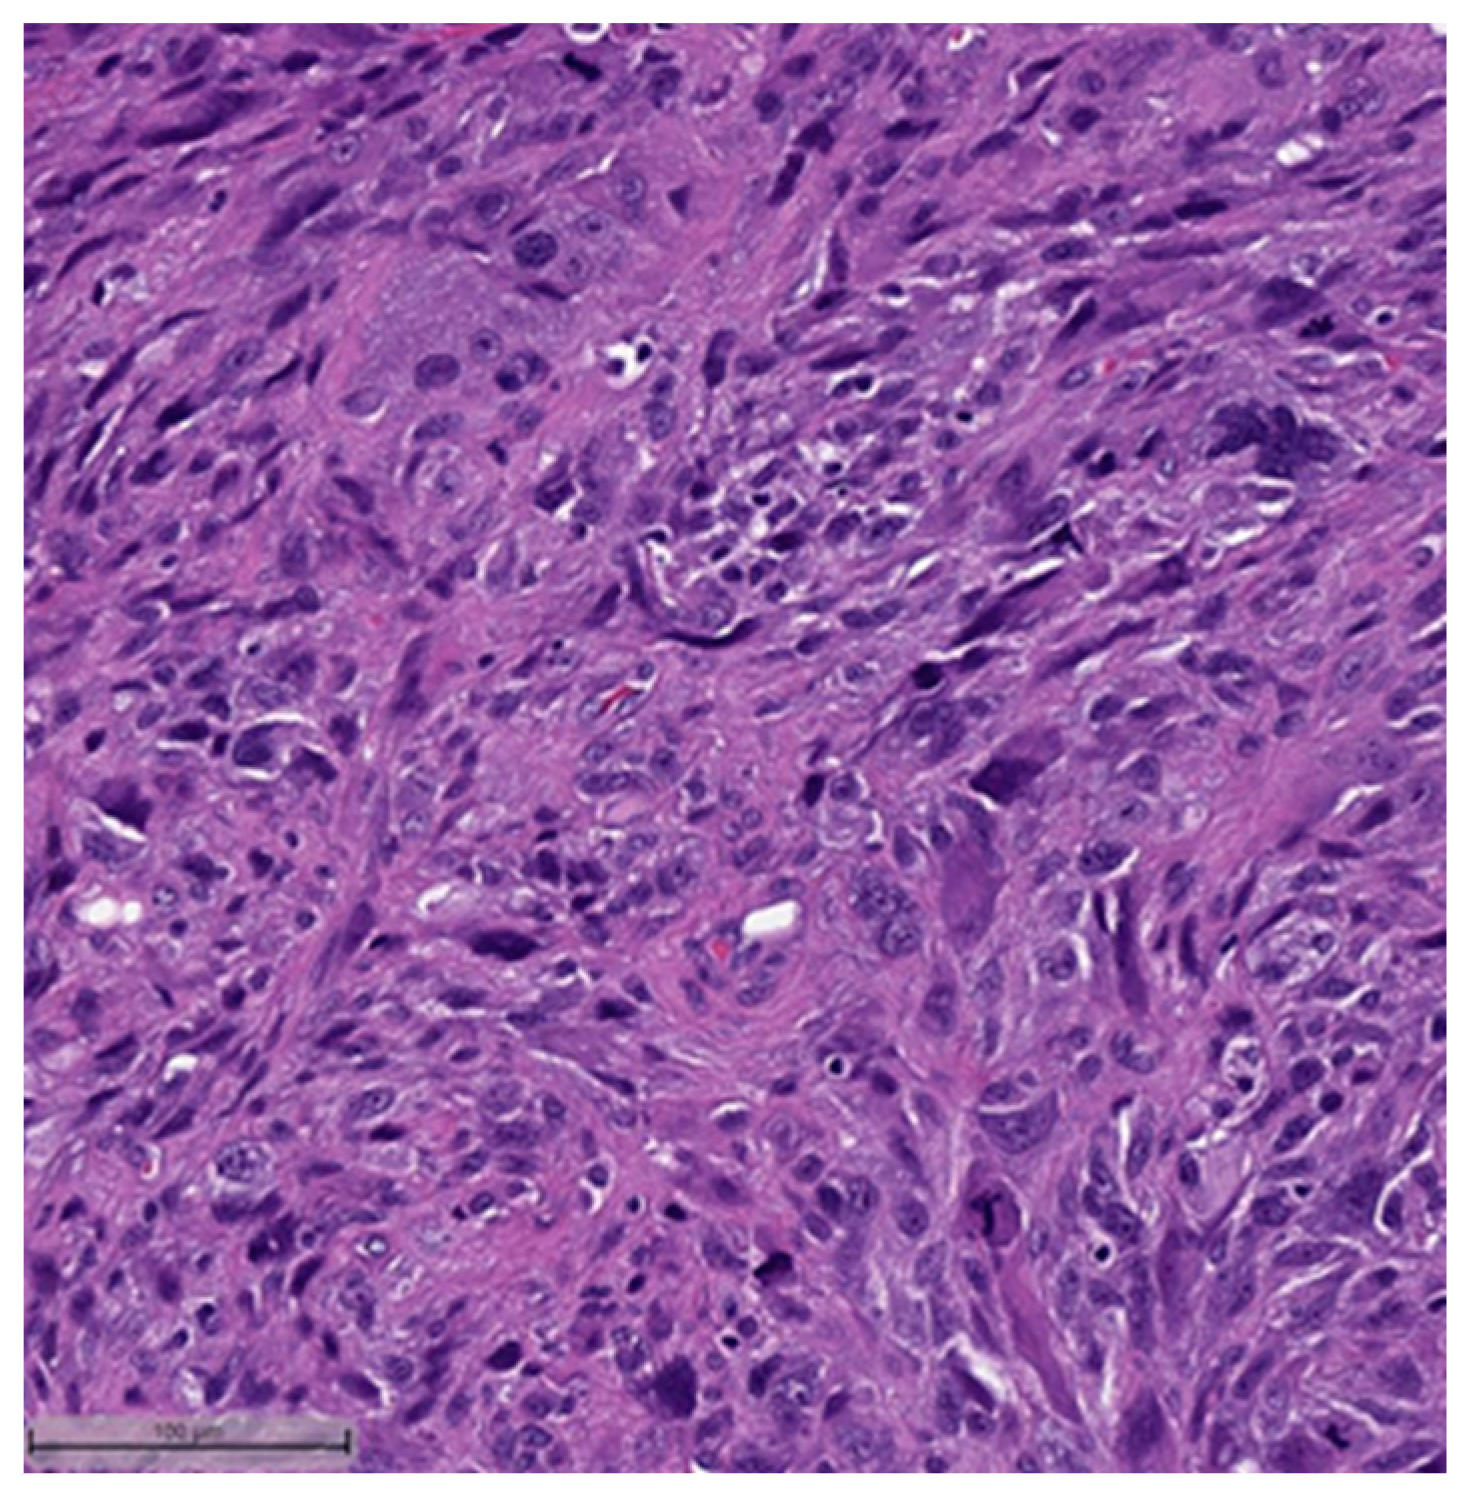

This system is primarily based on the specific metaplastic elements present within the tumors, while also highlighting the potential overlap that can exist between various histological subtypes [6]. Consequently, numerous cases diagnosed as MpBCs, are accompanied by a detailed description of the histological component or a combination of different component types and/or differentiations. The following figures illustrates a few examples: spindle cell carcinoma component with pleomorphic features (Figure 4), metaplastic breast carcinoma with chondroid differentiation (Figure 5), metaplastic breast carcinoma with a matrix-producing component (Figure 6), metaplastic breast carcinoma with osseous differentiation (Figure 7), and extensive trabeculae bone and hematopoietic tissue (Figure 8).

Figure 4.

Spindle cell carcinoma component with pleomorphic features (H&E, 20×).